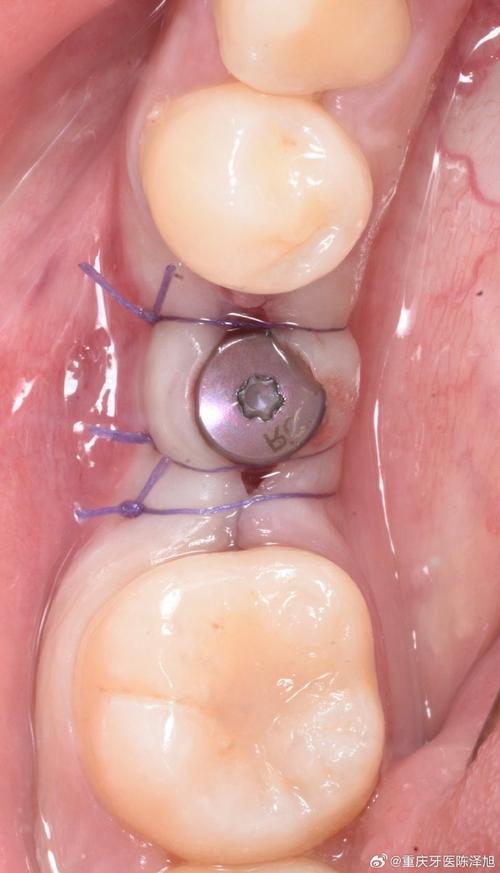

基台是种植牙的“中间连接件”,一端与植入牙槽骨的种植体(人工牙根)相连,另一端与上方牙冠衔接,承担传递咬合力、维持牙龈形态的重要功能,安装基台通常在种植体植入后3-6个月进行,此时种植体与牙槽骨已完成骨结合(达到稳定状态),手术过程大致包括:局部麻醉→切开牙龈暴露种植体→将基台与种植体连接→调整咬合后缝合牙龈,整个过程属于微创操作,时间通常为30分钟左右,具体时长根据牙龈厚度、基台类型等因素有所不同。